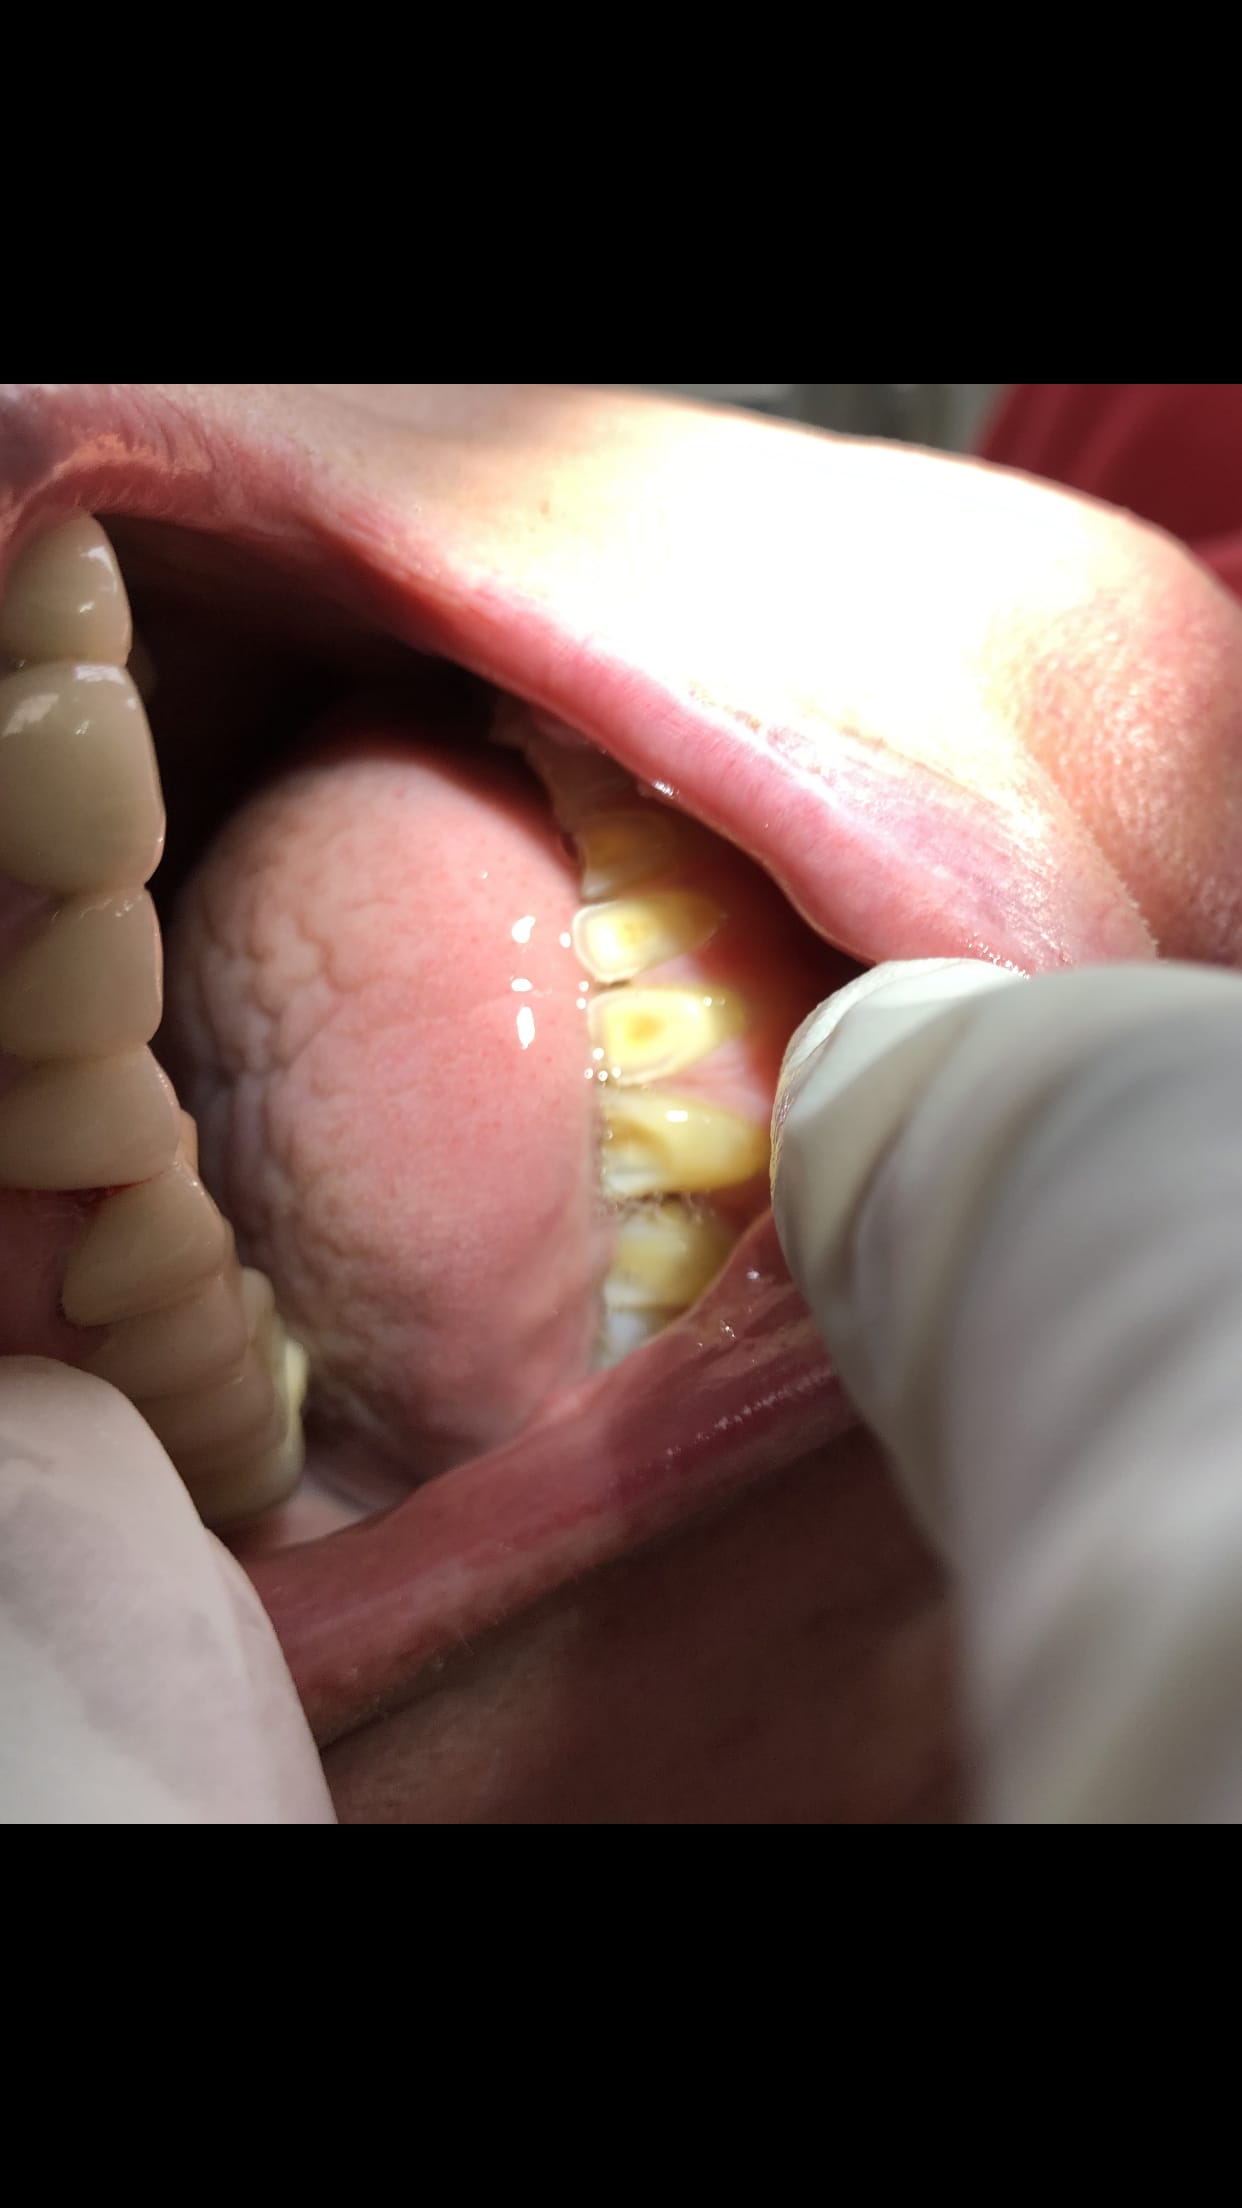

03/06/2019 à 10h18

Juste pour complément , photo de l arcade mandibulaire ... il aimerait évidemment que je fasse quelque chose .. je vous laisse imaginer le maxillaire avant traitement . Comme dit chocot29 oui j ai taille simplement parce qu elle était pas belle ...

B7fecfc4 c644 4f51 bd10 9e0b39d0528b cuooxh - Eugenol

9f9681ee 89b6 4e2b b7d7 8e6f278e8b1f q5hv1y - Eugenol